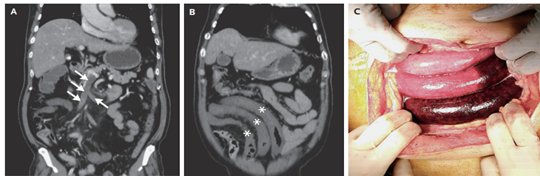

A 68-year-old man with cirrhosis presented to the emergency department with a 2-day history of severe abdominal pain. On PE, hypoactive bowel sounds, pain with palpation, and rebound tenderness throughout the abdomen were noted. CT of the abdomen with administration of contrast material showed thrombosis of the superior mesenteric vein ( A, arrows). A long segment of small bowel in the right lower quadrant of the abdomen showed increased wall thickness and decreased enhancement (B, asterisks). Cirrhosis of the liver and a few esophageal and paraumbilical varices were also seen. Owing to concern for bowel ischemia, an exploratory laparotomy was performed, during which dusky bowel extending from the distal jejunum to the proximal ileum was seen (C). A diagnosis of acute superior mesenteric vein thrombosis complicated by small-bowel infarction was made. Resection of the infarcted bowel, transvenous thrombolysis and thrombectomy, and a primary anastomosis were performed. The patient was discharged home on postoperative day 14 with a prescription for long-term apixaban. An extensive workup for causes of mesenteric vein thrombosis identified only the patient’s known cirrhosis. At a 5-month follow-up visit, he was doing well, and imaging showed resolution of thrombosis; he has continued to receive long-term anticoagulation therapy